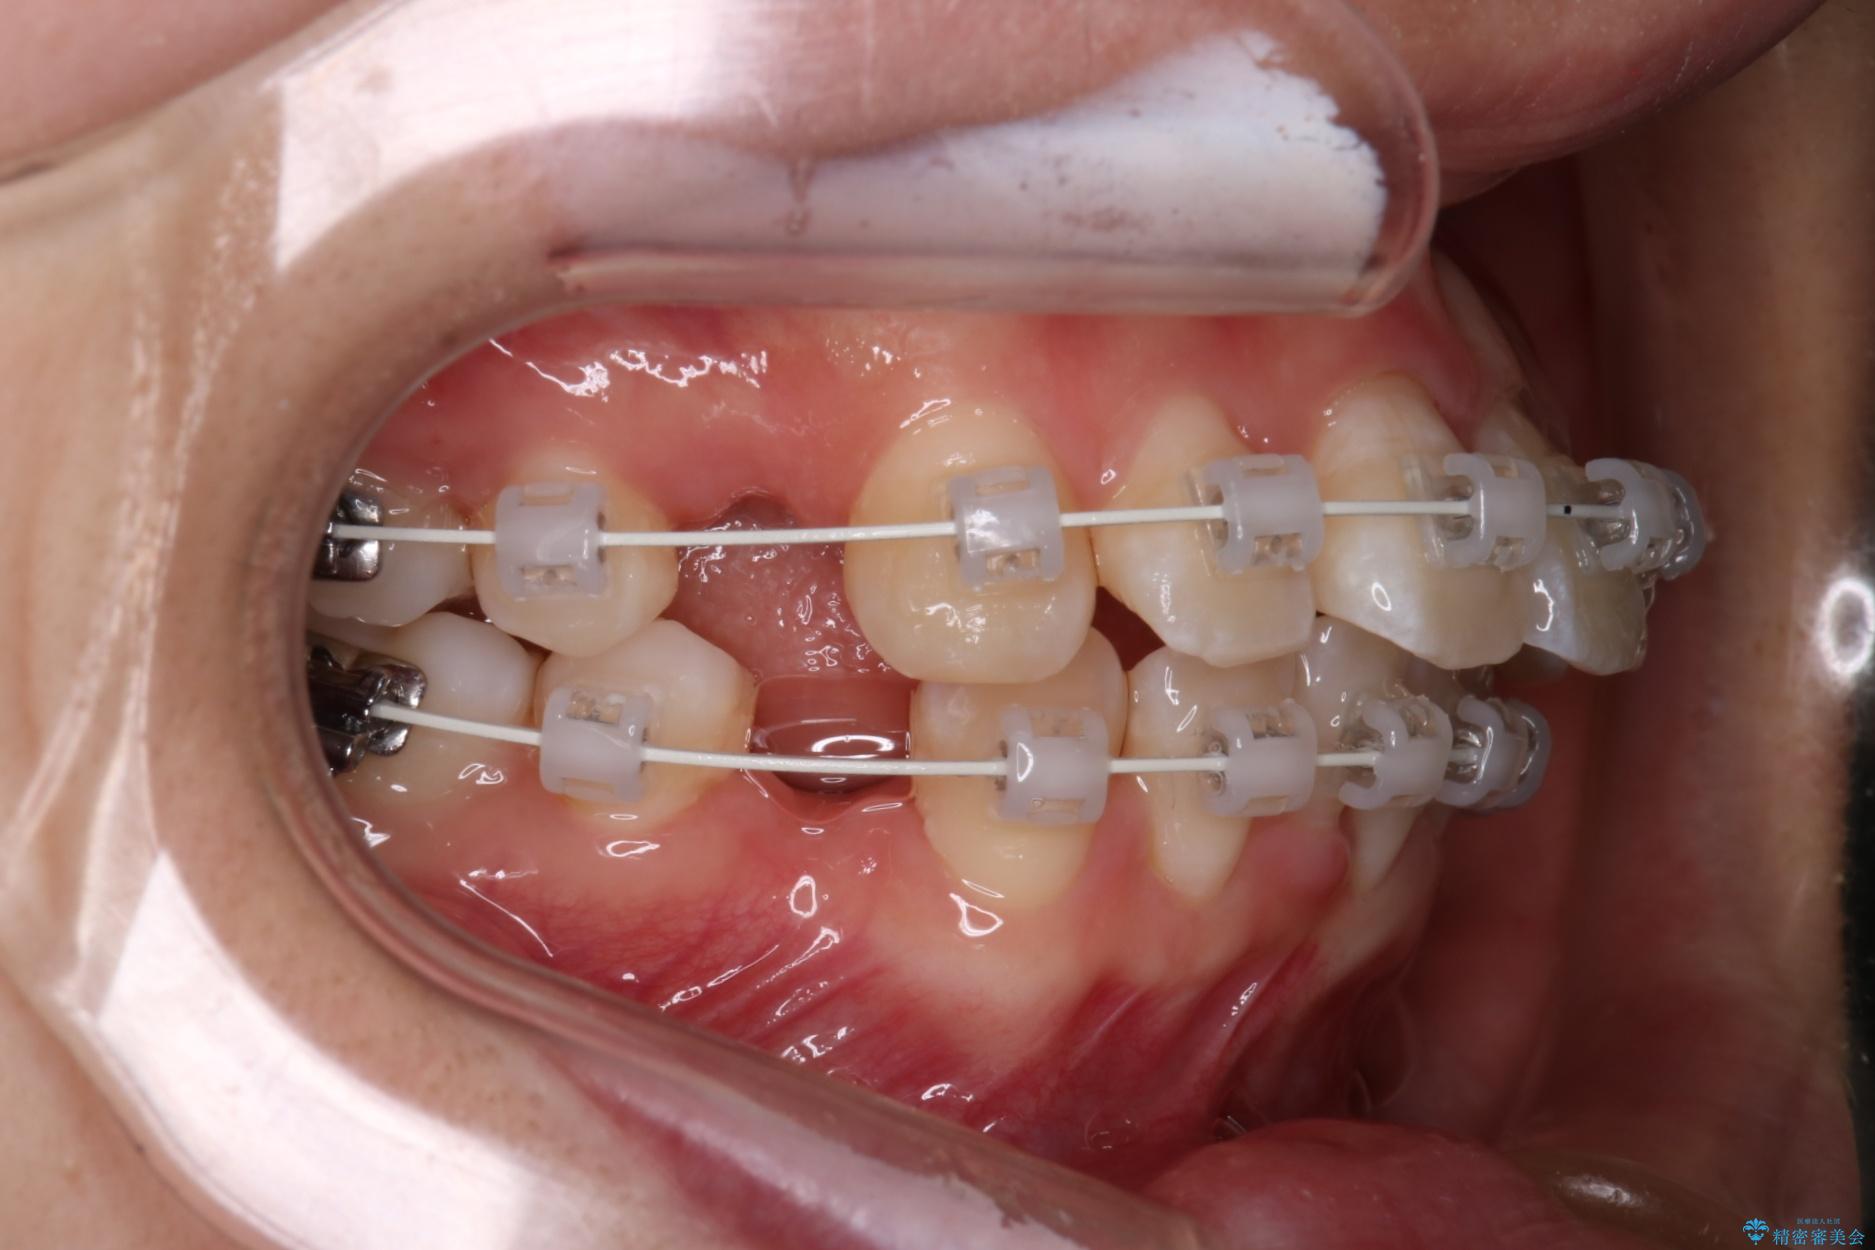

上下4番目の歯を抜歯してガタつきを改善しながら口元を下げる治療計画を立てました。

- 1年9ヶ月

- 96.8万円